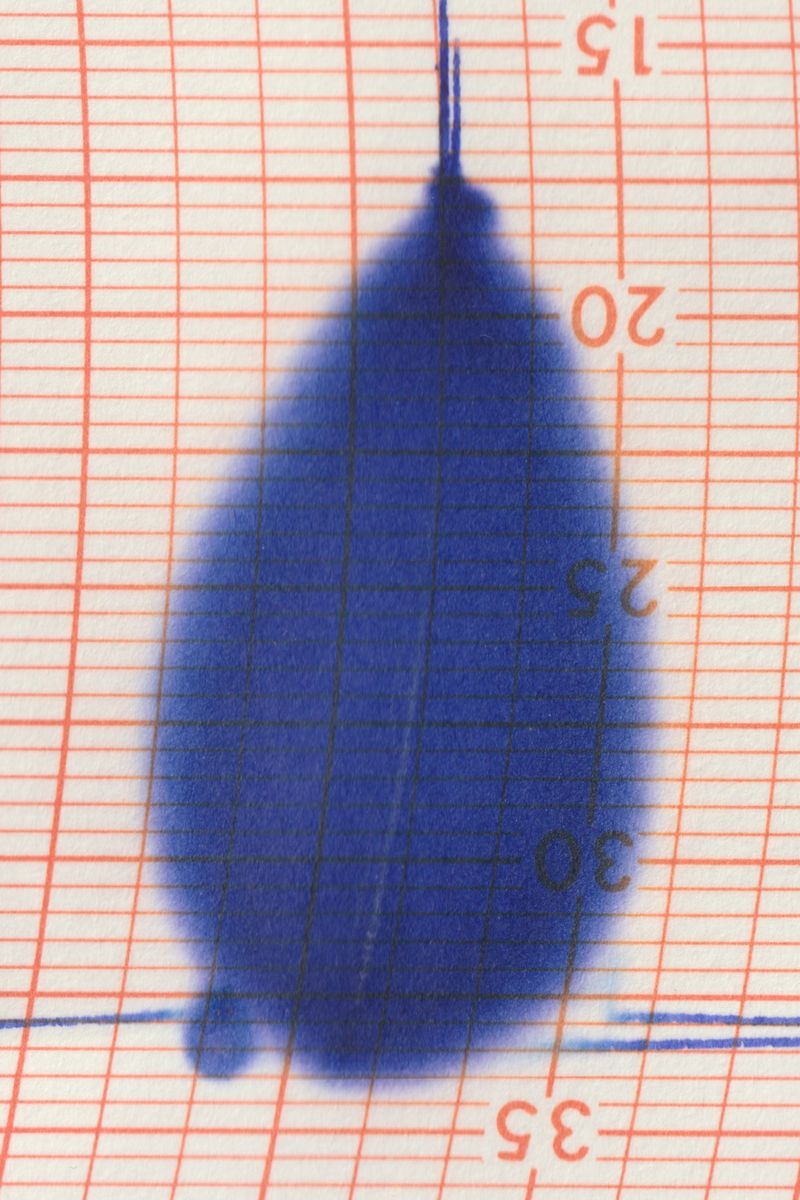

Following a terrifying experience with a too high dose of LSD when I was 16, something has changed in the way I observe visible reality. A hypertrophic screen materialized between me and the world, a scar of opacity. The fear of hallucination teaches a new language, so that every meaning remains trapped in a net and only the signifier filters through its meshes. No shadow, only empty light. Anguish arrests every retinal projection on that screen. Every perception is immobilized to be inspected for a hallucinatory return, it is reified, detached from its real referent, reduced to representation, incapable of referring to something outside of it. And behind (or in front) of it, the eyes have stolen consistency from reality. The body only appears occasionally, at the edges of the mind, when we engage in apperception. And yet I feel the tinkling of a gear that draws my attention inside my eye. I reflect on myself, I look back and from the inside. Once vision is situated in the empirical immediacy of the body, it belongs to time, to flow, to the end.

When we learn to speak, we are immersed in systems of discourse that pre-exist us and will survive us. So it is with seeing. Between us who observe and the world, there is inserted the set of discourses that constitute visuality and that make it different from vision. Between the retina and the world, a screen of signs is inserted, a screen composed of all the multiple discourses on vision constructed in the arena of collectivity. This screen casts a shadow, Jacques Lacan calls it “scotoma”, “a stain”. Because when we look through the screen, what we see is trapped in a net and can only project towards us the shadow itself of its signifier, its meaning. In the visual field, something cuts, cuts through, parallel to the pupil. It is the fabric of practices, habits, languages, all linked to the reality of representations, with which the meaning of what we see is casted as a shadow.